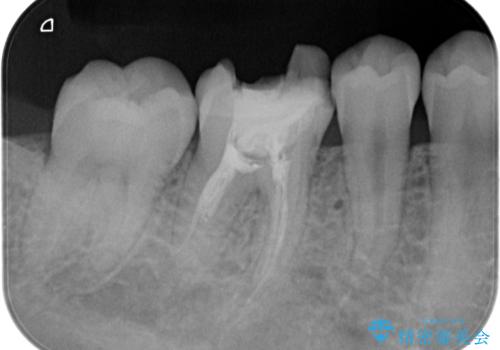

【根管治療】ラバーダムと顕微鏡を用いた治療

- 奥歯の治療の継続を主訴に来院された患者様です。

他院にて根管治療を行ったそうですが、ラバーダムを使用していなかったため、クラウン修復の前に当院の治療を希望され受診されました。

根管内に充填されている材料は、スカスカの状態で簡単に除去ができました。

術後1年経過を見ていますが、問題なく良好な経過をたどっています。